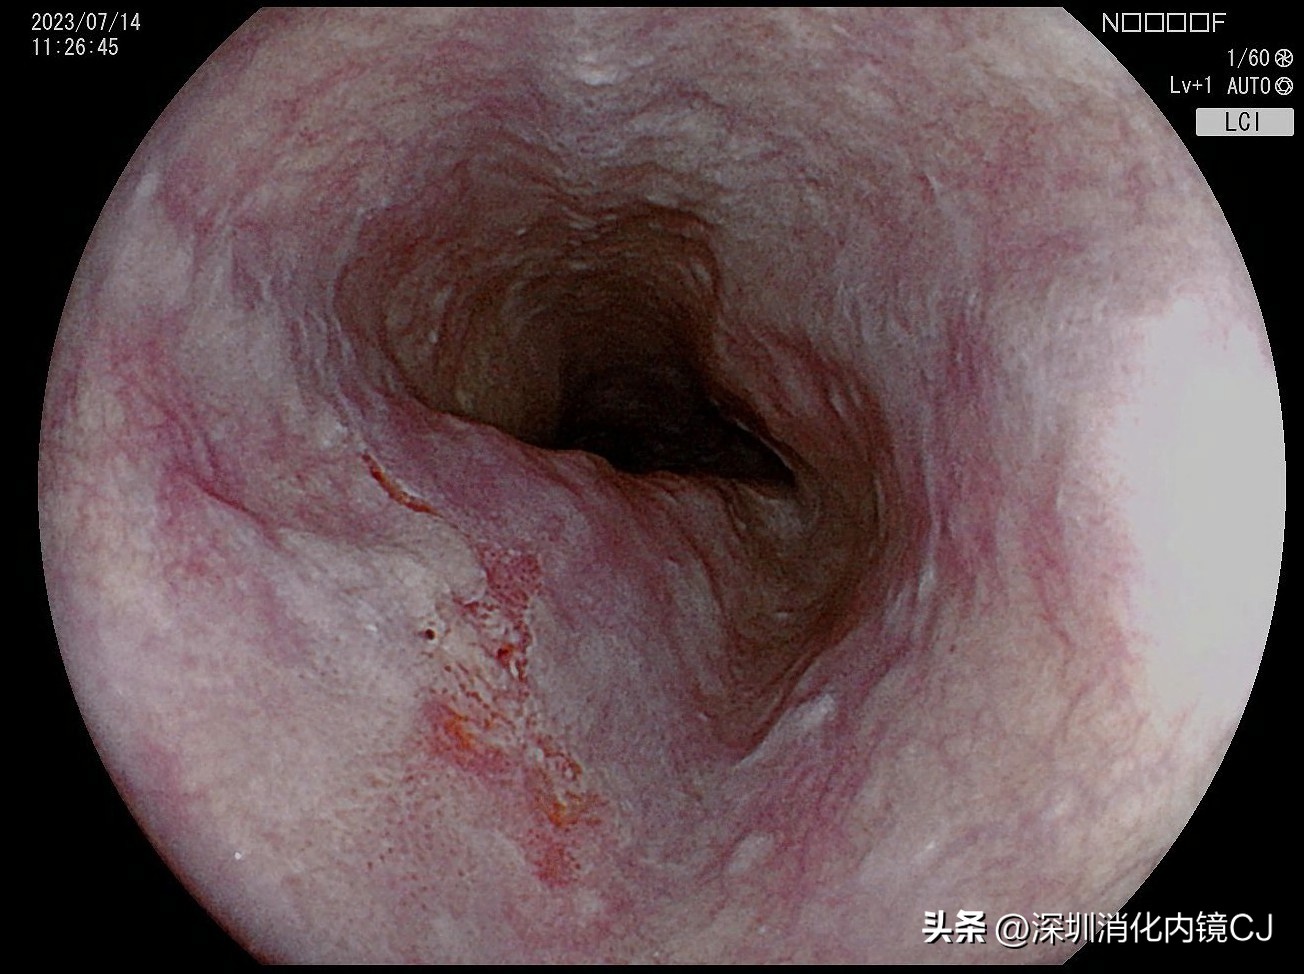

LCI模式进镜发现可疑病变

69岁,男性,因胸腹部不适来我科行胃肠镜检查,胃镜过咽部在食管距离门齿22-25cm处发现可疑病灶,经色素内镜、增强内镜、放大内镜仔细观察后,非常自信地诊断为早期食管癌,浸润深度黏膜内(m),可以行内镜下ESD切除。